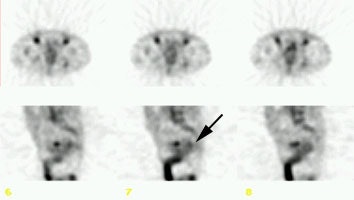

Staging colorectal carcinoma: The patient shown below had a large rectal cancer (white arrows on CT scan) and the CEA scan was done for staging purposes to assess for metastatic disease. Tracer uptake can be seen in the primary lesion (black arrow posterior to a small amount of urinary bladder activity), but no other sites of abnormal activity were identified. |

|